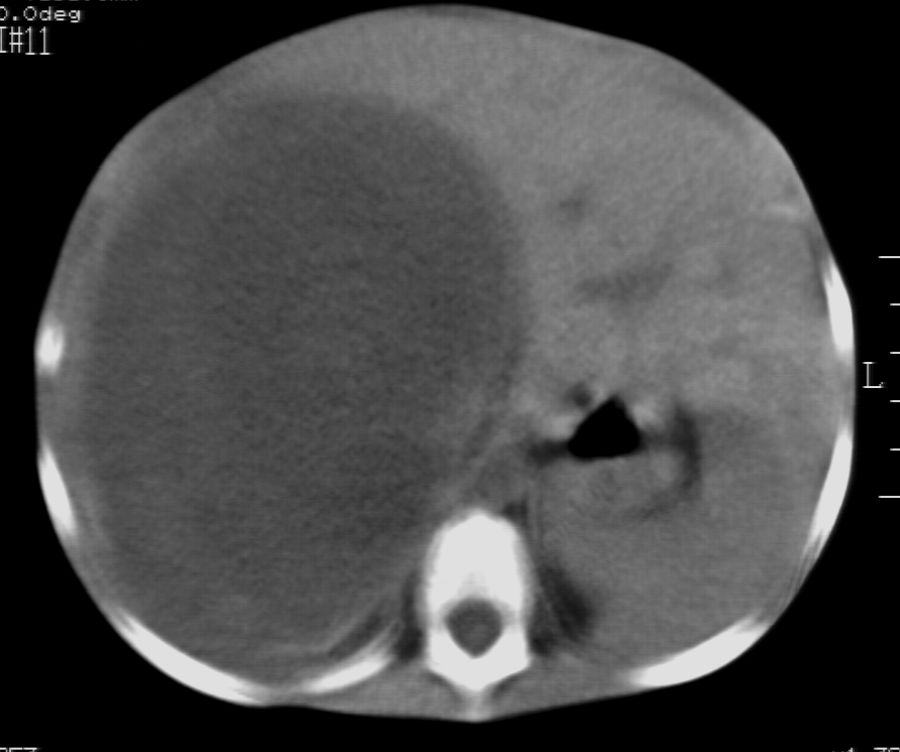

标题: PED2927:马某,男,两岁,发现血尿4天,请大家看看,发表 [打印本页]

标题: PED2927:马某,男,两岁,发现血尿4天,请大家看看,发表

右肾巨大囊性占位病变,其内密度不均,正常肾结构消失,肝脏,肾上腺及肠管等受压移位。双肺内多发大小不等的结节及块状影。考虑右肾母细胞瘤伴双肺多发转移。

肾母细胞瘤(wilms),系儿童最常见的恶性肿瘤,好发于3岁以下儿童,瘤体较大,主要由胚胎性肉瘤样细胞和上皮样细胞构成,临床以腹部肿块;血尿和高血压为主要体征。